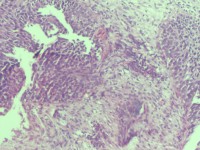

宫颈活检组织

性别

女

年龄

43岁

临床诊断

宫颈病变

一般病史

宫颈癌筛查:hpv16(+))

标本名称

宫颈组织

大体所见

灰白色组织

老师们看看,高级别累腺吗